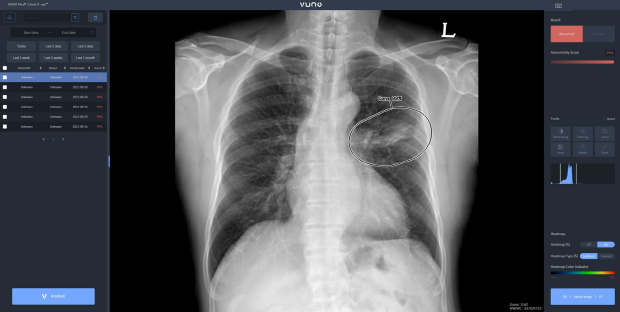

우즈베키스탄 군 병원에 도입된 솔루션은 뷰노의 AI 기반 상지 엑스레이 판독 보조 솔루션 ‘뷰노메드 익스트리미티 엑스레이™(VUNO Med®-Extremity X-ray™)’와 이동형 엑스레이 장비에 AI 기반 흉부 엑스레이 판독 보조 솔루션 ‘뷰노메드 체스트 엑스레이™(VUNO Med®-Chest X-ray™)’를 탑재한 패키지 제품이다.

또 이동형 엑스레이 장비에 뷰노메드 체스트 엑스레이™를 탑재한 패키지 제품은 별도의 차폐 시설 없이도 다양한 상황에서 쉽게 환자의 흉부 엑스레이 촬영이 가능한 제품이다. 인공지능을 기반으로 수 초 이내에 판독 결과를 제공해 의료 환경의 판독 효율성과 정확도를 크게 높인다.